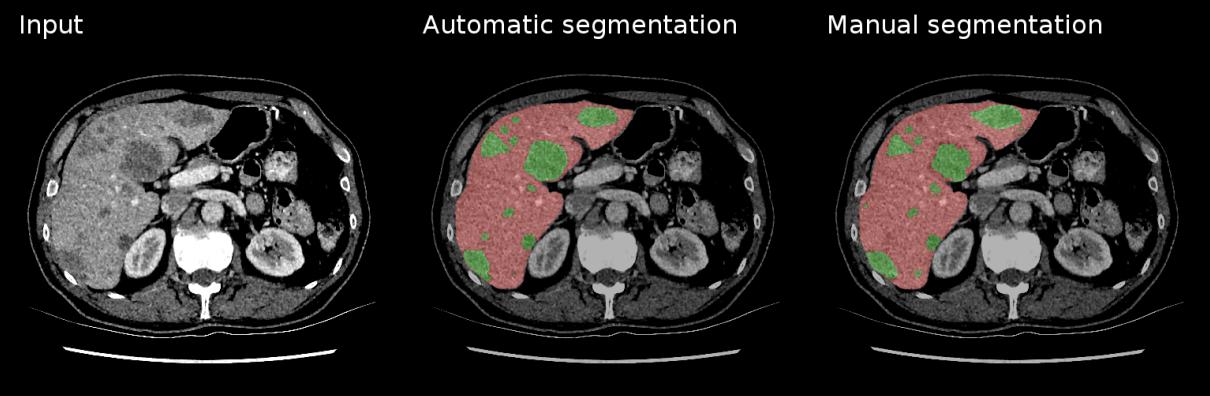

LiTS17 is a liver tumor segmentation benchmark, with data and segmentations provided by clinical sites around the world. The training dataset contains 130 CT scans and the test dataset contains 70 CT scans.